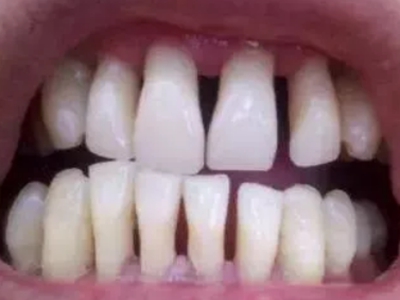

牙龈退缩牙根出现三角形空隙图

牙龈退缩牙龈出现萎缩,逐渐远离牙颈部,牙齿被牙龈覆盖的面积减小,牙根暴露,牙根间隙露出形成黑三角,牙根部呈黄色,牙龈敏感,影响咀嚼。